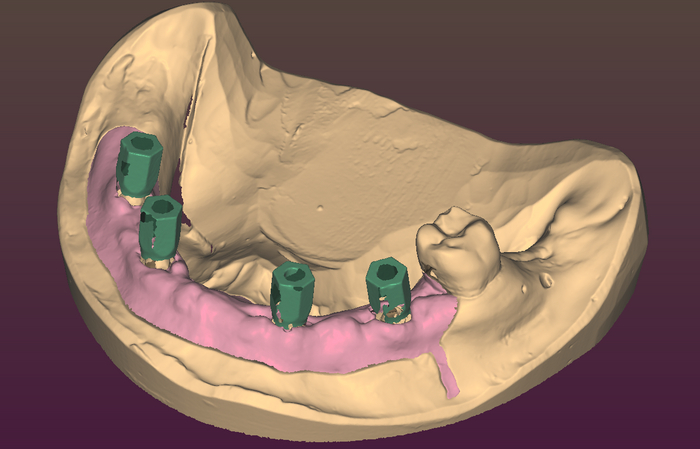

Балку получил из фрезерного центра, теперь надо её проверить на качество "посадки" на аналоги имплантов и в случае если будет баланс припассовать.

Титановый каркас "сидит" как надо не качается и не балансирует; не только на лабораторной модели, но и в полости рта — можно продолжать.